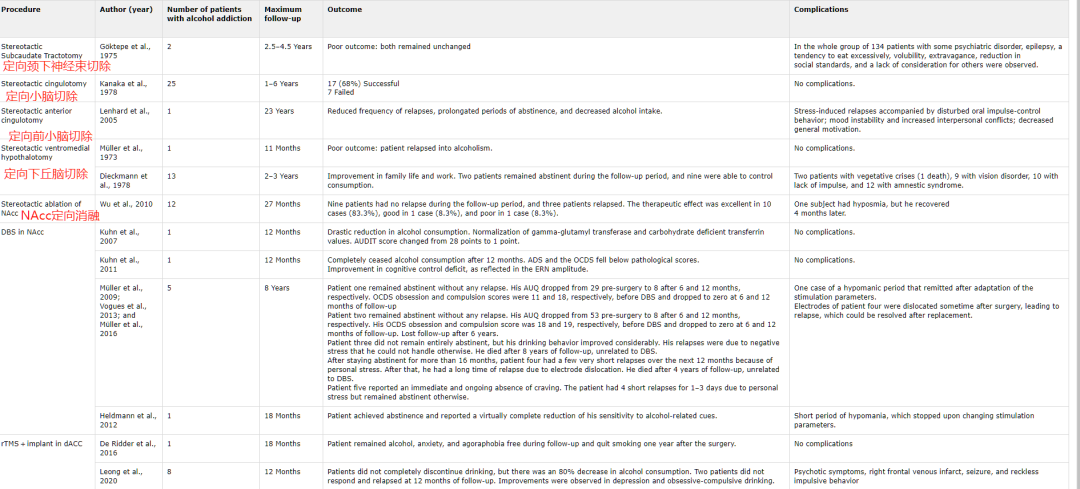

最近一篇文章回顾了使用神经外科手术治疗酒精使用障碍的研究。

de Almeida, B. V., & da Silva, L. J. (2022). Neurosurgery in the Treatment of Alcohol Use Disorder: A Systematic Literature Review. Arquivos Brasileiros de Neurocirurgia: Brazilian Neurosurgery, 41(01), e76-e84.

可以看到这样的研究并不多。神经外科手术仅在某些特殊情况下才可以在酒精成瘾治疗中起到辅助作用。例如,一些研究表明,在执行特定的脑手术(例如,脑深部刺激)后,患者的酒精摄入量减少。但是,这种手术并不是为所有患者都适用的,并且需要经过严格的评估,以确定是否适合患者。另外,手术还可能造成一些已知或未知的并发症。因此,目前最有效的治疗酒精成瘾的方法仍是药物治疗和行为疗法。